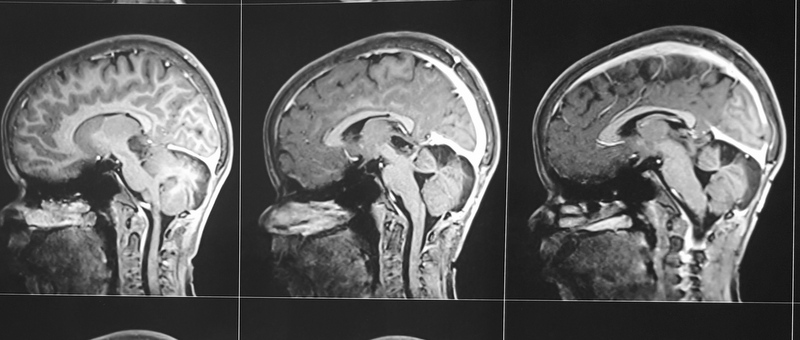

ICA Bifurcation Aneurysm

A 38-year-old-male was admitted with sudden onset of severe global headache and vomiting, followed by altereation in sensorium. CT brain showed subarachnoid and intraventricular hemorrhage (Fig 1). MRI brain revealed deep seated right sided thalamic hematoma due to ruptured internal carotid artery bifurcation aneurysm (Fig 2), confirmed by cerebral digital subtraction angiography (Fig 3). He underwent clipping of the aneurysm by transciliary supraorbital keyhole minicraniotomy (see video). Postoperative angiography showed complete occlusion of the aneurysm (Fig 4). When discharged ten days later, there was no neurological deficit (Fig 5).

Fig 2

(Fig 2)